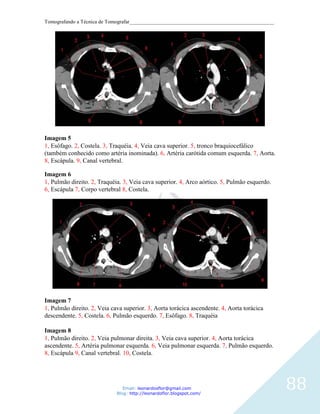

Imagem 5

Corte axial. 1, Concha. 2, Seio maxilar. 3, Asa lateral do processo pterigóideo. 4,

Nasofaringe. 5, Atlas (C1). 6, Fenda do palato ptérigo.

Imagem 6

Corte axial. 1, Seio maxilar. 2, Apófisis pterigoides,. 3, Nasofaringe. 4, Mandíbula. 5, Arco

45

anterior do atlas. 6, dente do áxis (Processo odontoide).